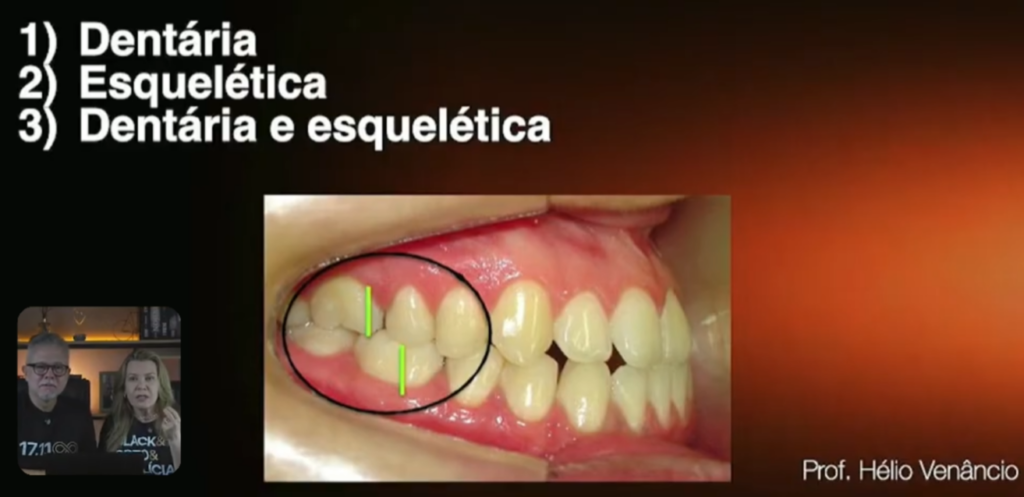

A classe 3 que nós vamos tratar aí, ela é dentária? Ela é esquelética? Ou ela é as duas coisas?

Essa boquinha que vocês estão vendo aí, o paciente é um padrão 3 ou é só uma mordida cruzada anterior?

Vocês estão percebendo que aqui, o molar está engrenadíssimo de classe 1:

Só que nós temos um problema um pouco mais sério aqui no anterior, que é uma mordida cruzada. Quantas vezes nós já vimos colegas falando assim: ah, vamos fazer, num caso como esse aqui, uma

É a gente manipular em relação cêntrica. Muitas vezes, você vai ver que ele é classe 1. Ele não é uma classe 3, é uma pseudo classe 3.

E respondendo a essa pergunta, na verdade, esse paciente não é classe 3, não é padrão 3.

Ele apenas tem a mordida cruzada anterior.

Ele é um paciente padrão 1, classe 1, com a mordida cruzada anterior por conta da inclinação lingual.

Por causa da inclinação superior lingual dos incisivos e por causa da inclinação vestibular dos incisivos, significa que quando nós falamos que o problema é por causa de inclinações dentárias, significa que esse problema, é um problema só dentoalveolar.

E se ele é um problema só dentoalveolar, é muito mais fácil de corrigir!